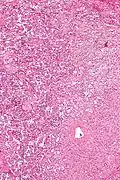

Micrograph of a gangliocytic paraganglioma. H&E stain.

A gangliocytic paraganglioma is a rare tumour that is typically found in the duodenum and consists of three components: (1) ganglion cells, (2) epithelioid cells (paraganglioma-like) and, (3) spindle cells (schwannoma-like).[1]

GP consist of three components (1) ganglion cells, (2) epithelioid cells (neuroendocrine-like), and (3) spindle cells (schwannoma-like). The microscopic differential diagnosis includes poorly differentiated carcinoma, neuroendocrine tumour and paraganglioma.[1]